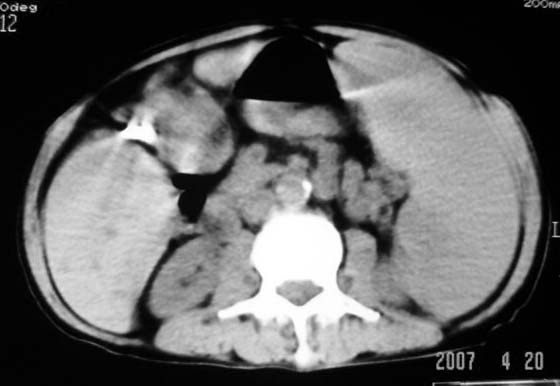

以下是引用dyqct在2007-4-20 16:38:00的发言:[br]考虑:1、巨脾;[br] 2、肝内多发低密度,首先考虑转移瘤;[br] 3、胆囊多发结石。

以下是引用andymaomao在2007-4-20 16:47:00的发言:[br]肝脾增大,肝内胆管扩张,且可见多发小囊性低密度灶,胆囊窝区高密度影,手术化疗病史,贫血....[br]1.肝脾大及贫血与术后化、药疗有关;[br]2.胆囊窝区高密度影,术后改变?肝内胆管扩张,积液?[br]3.肝内多发低密度灶,性质?建交增强